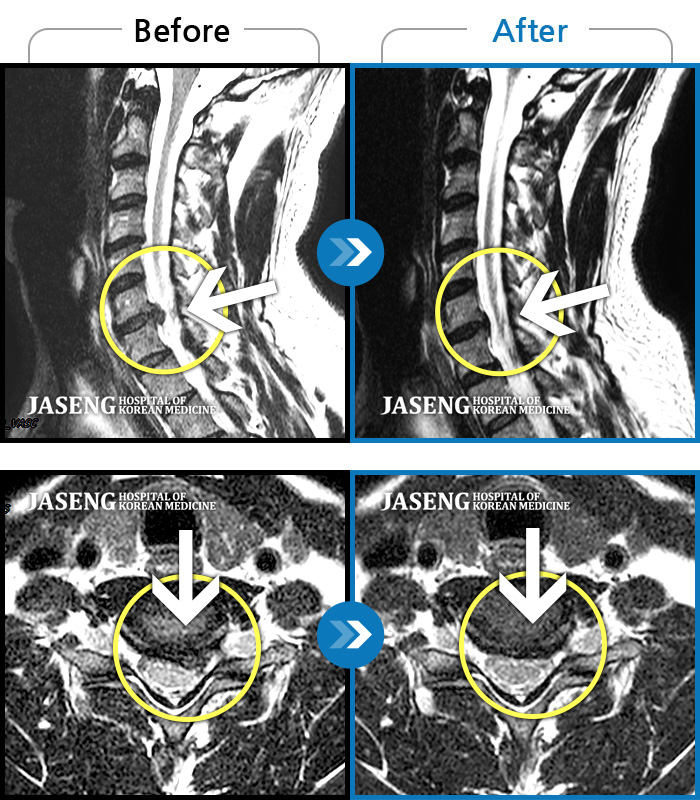

목디스크

강남 · 강만호 원장

양측 승모근 통증과 목 통증, 견갑골 통증으로 고개를 돌릴때 통증을 호소하는 환자였습니다.

촬영시기

2019.11.18 ~ 2024.07.30

2024.08.09

조회수 478